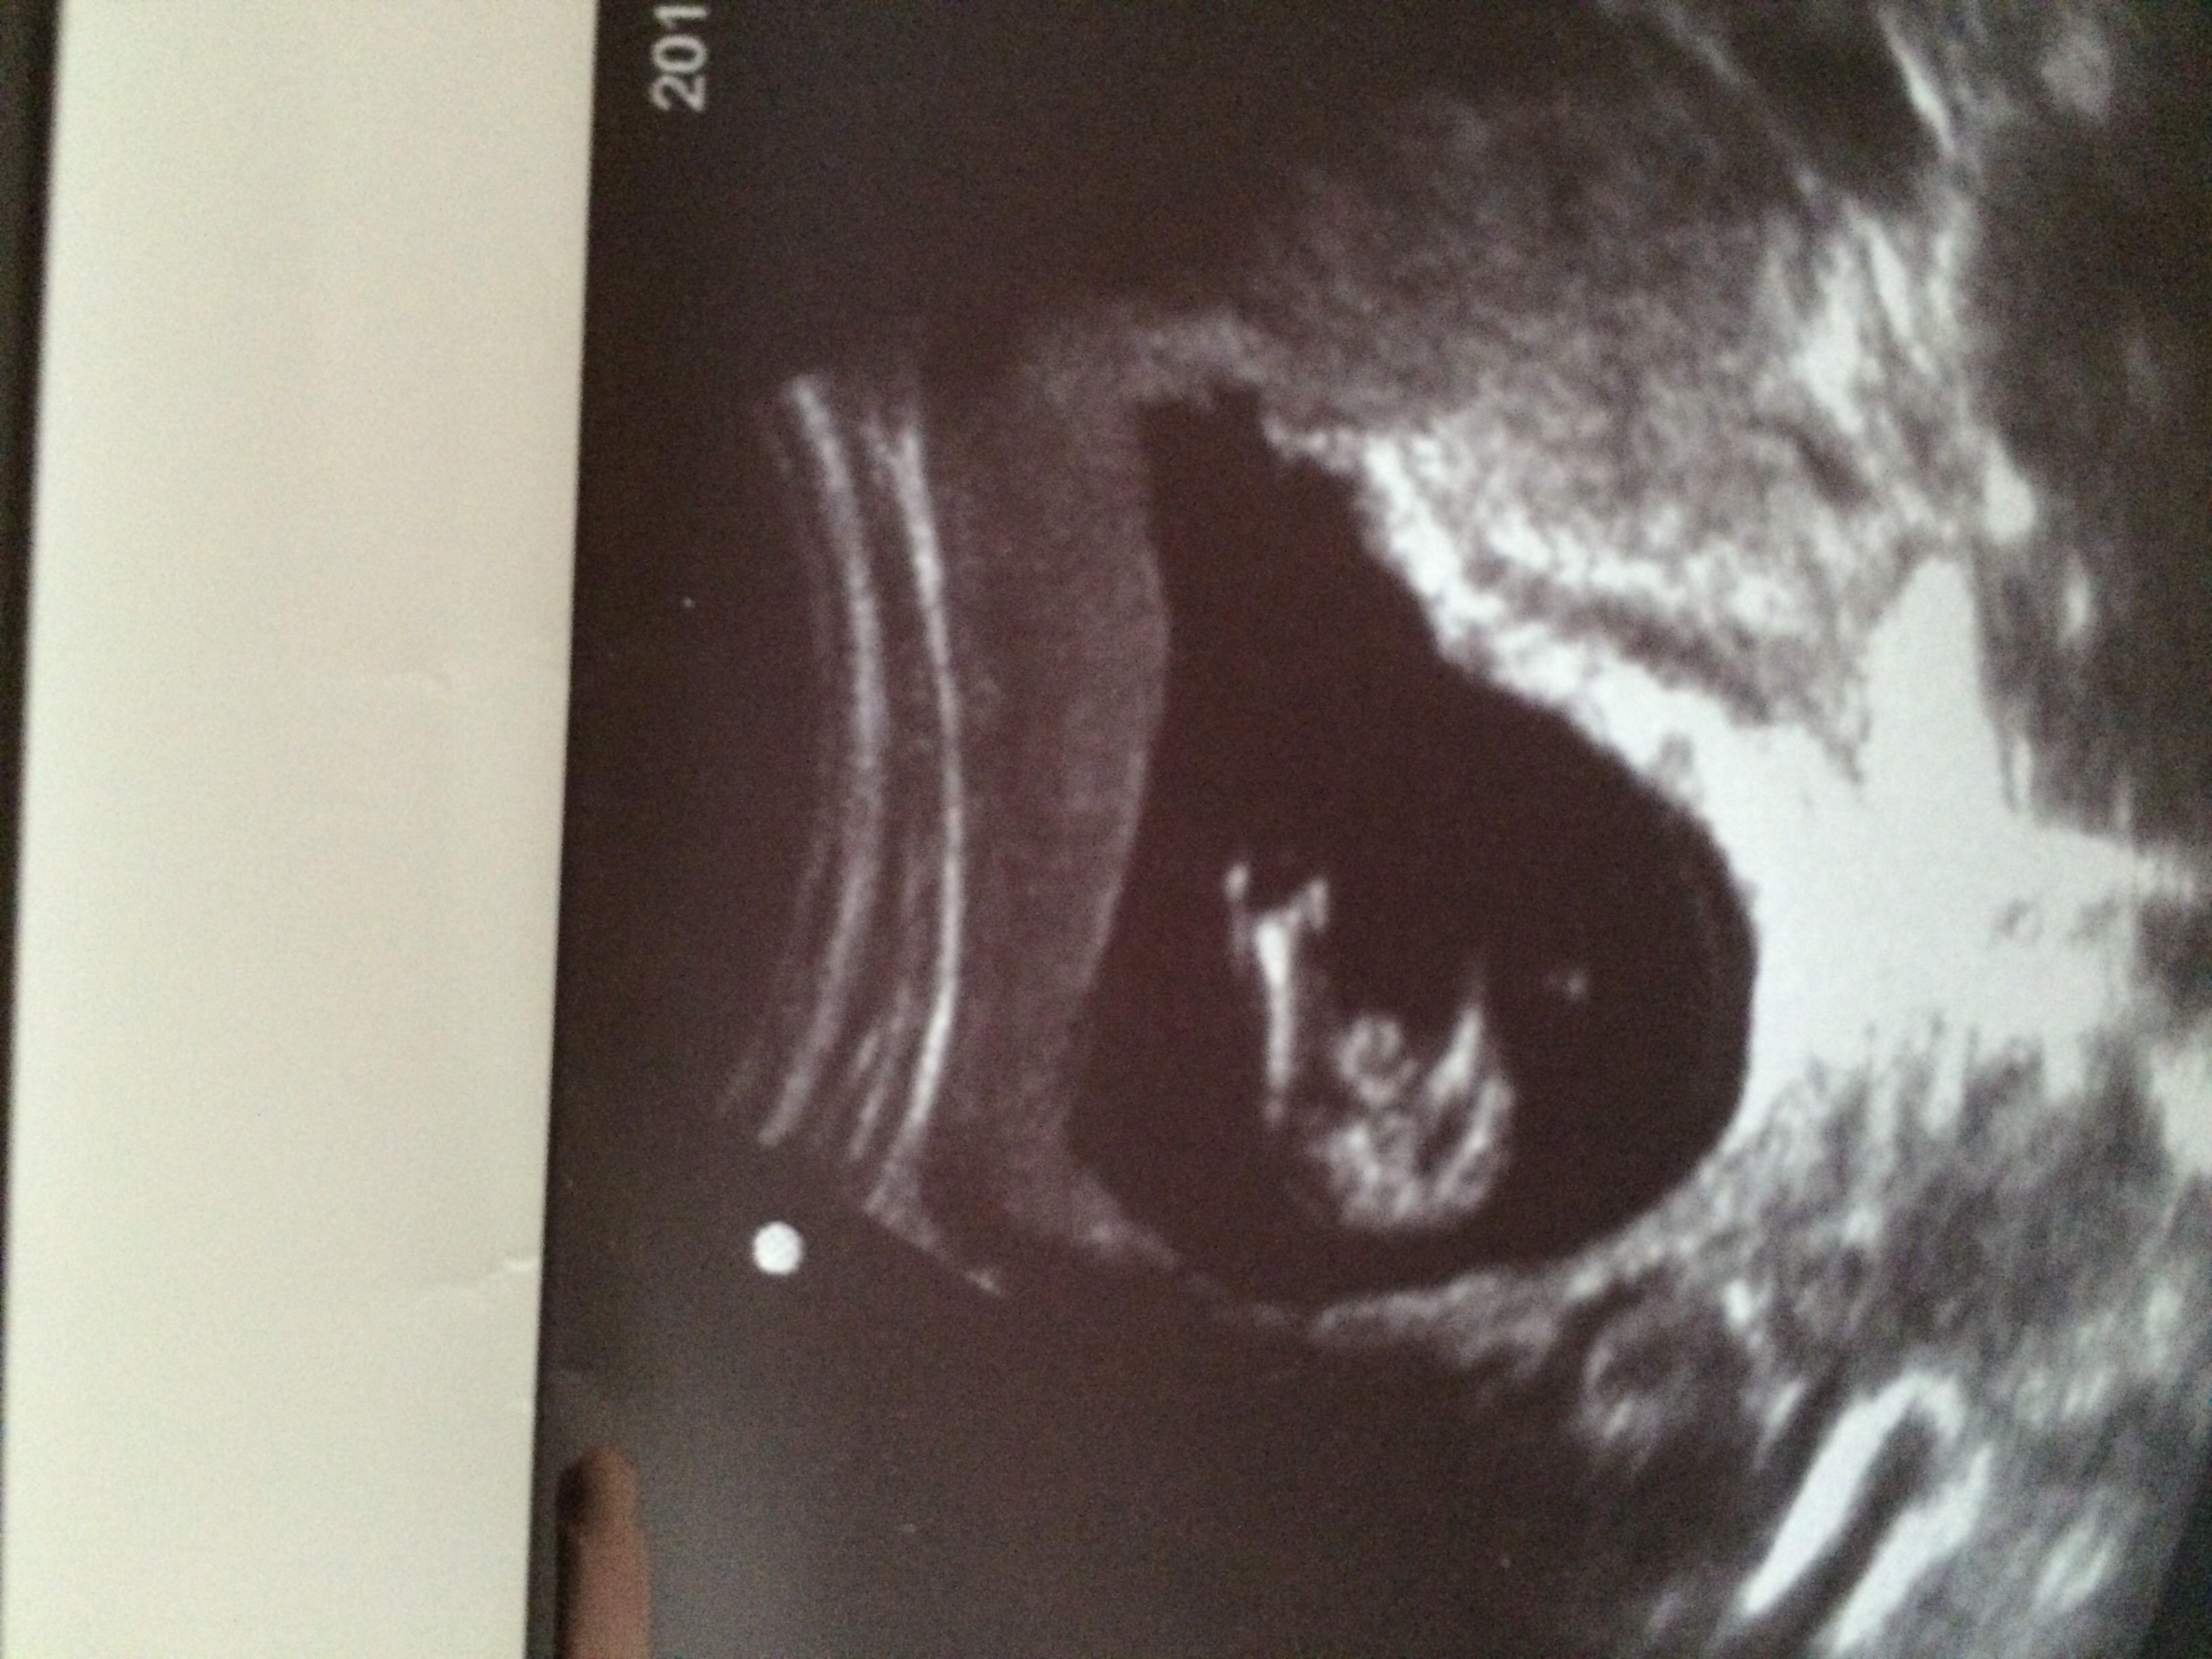

Attachment 28450Attachment 28451

I do not have any profile/nub shots.

Id say Boy!

I'd say a very proud young man.

Definitely looks like a boy to me! :) :superhero:

I would say boy!

Looks like a boy to me!

Yup boy to me too

Confirmed BOY!!!